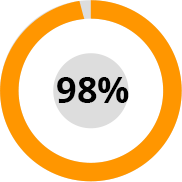

Az ízületi betegségek megelőzésének világszervezeti nemzetközi kutatóközpontok hat hónapon át elvégeztek számos klinikai vizsgálatot és alapkutatást a HondroLife spray készítményen. 2500 önkéntes vett részt a kutatásban.

A tesztek eredményeként kiderült: